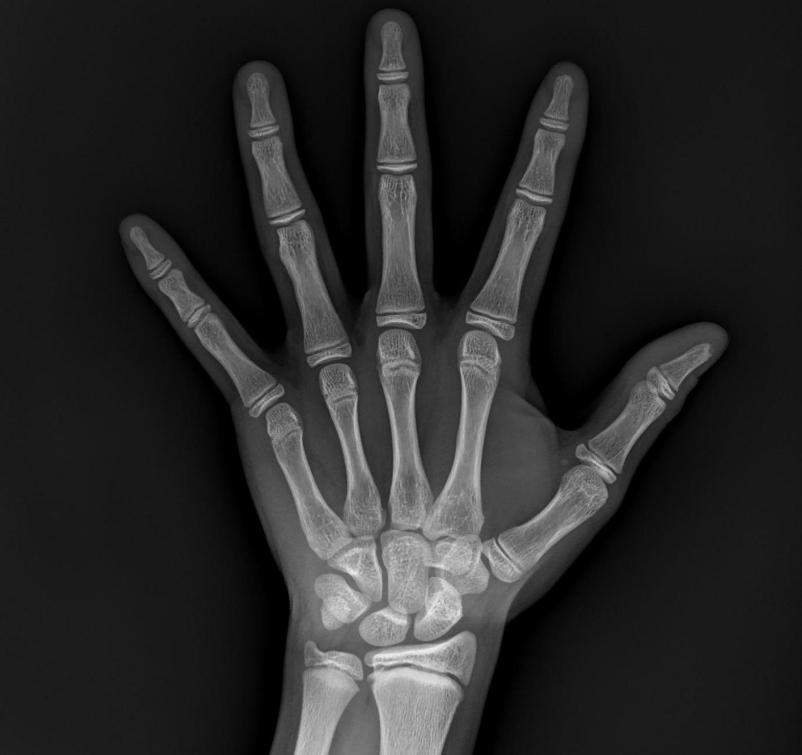

要想判断孩子是不是骨龄偏大,最简单的方法就是去测个骨龄。带孩子到当地有拍摄X光片能力的医院,去拍个左手正位片,然后拿给我们生长发育科室的医生来评估,就可以知道孩子的骨龄到底是什么程度,如果偏大,到底偏大了几岁。